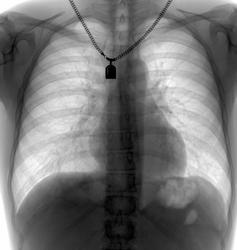

Молодая барышня 28 лет. На момент проведения ц ФГ жалоб нет. Представлена для контроль аналоговая рентгенограмма двухнедельной давности. Динамика отсутствует (посему не выставляю)

В тот же день проведена КТ (о результате информирован лечащим врачом). Ваше мнение?

Шаровидная тень: в S4 в/доли слева (1 случай) и S10 н/доли справа (2 случай)

Татьяна Валентиновна, асолютно согласен. что основной рентгенологический признак - шаровидные тенеобразования, но...достаточно ли они "шаровидны" и достаточно ли однородны....+молодой, в общем то возраст, + отсутствие существенных жалоб. Конечно, смущает тот факт, что это не первые их ФГ (но у меня то они впервыеwink). Опять же - в С10 (скрывается за тенью печени), в С4 слева (не факт, что раньше было перекрыто левым краем сердца) и, как следствие - не были обнаружены.

Внутрилегочная секвестрация или артериовенозная мальформация.

..... артериовенозная мальформация.

Она самая))). Да, оба случая подтверждены на КТ.